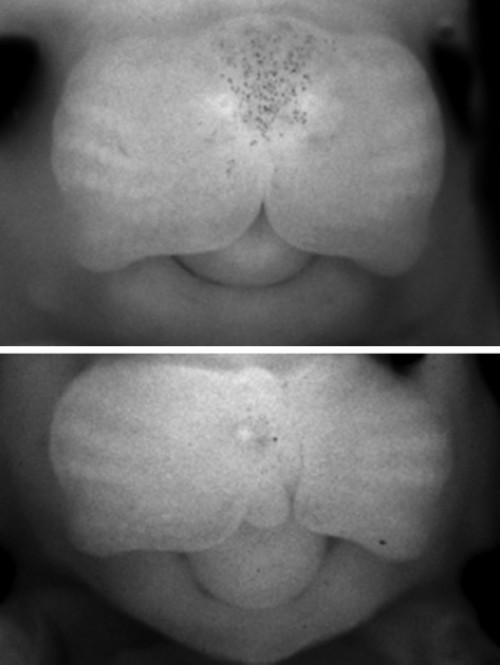

為了使這一個(gè)基因突變序列的解碼正確無(wú)誤,研究人員制備了缺乏這段DNA序列的轉(zhuǎn)基因小鼠,因?yàn)榛蛐蛄行∈蠛腿祟?lèi)中的作用方式非常相似,因此這段序列很可能在兩個(gè)物種中具有相同的作用。他們發(fā)現(xiàn),這些轉(zhuǎn)基因小鼠面部有輕微的變化,如一個(gè)更短的鼻子,也有一些小鼠發(fā)生唇裂。科學(xué)家們也利用這個(gè)小鼠模型來(lái)調(diào)查,胚胎發(fā)育期間發(fā)生了什么事情導(dǎo)致了這些變化。這一段位于人體第8號(hào)染色體上的DNA序列包含一些調(diào)控因子,這些調(diào)控因子可以控制發(fā)育面部中的Myc基因表達(dá)。刪除這一區(qū)段,會(huì)導(dǎo)致小鼠面部形態(tài)的輕微變化,偶爾發(fā)生CL/P。”在分子水平上,研究人員確定了幾個(gè)下游基因的錯(cuò)誤表達(dá),強(qiáng)調(diào)了它們對(duì)顱面發(fā)育網(wǎng)絡(luò)的組合影響,和細(xì)胞促成未來(lái)上唇的一般代謝能力。這種雙分子病因,可以說(shuō)明8q24區(qū)段對(duì)人類(lèi)面部畸形的突出影響。研究人員發(fā)現(xiàn),在缺乏該DNA片段的小鼠胚胎面部中,Myc大部分變得失活。這反過(guò)來(lái)又影響兩組基因:直接參與構(gòu)建面部的基因,和制造核糖體(細(xì)胞的蛋白質(zhì)生產(chǎn)工廠)的基因。后者的作用可以使發(fā)育中的上唇對(duì)其他遺傳疾病和環(huán)境因素(如在懷孕期間吸煙或飲酒)更敏感,這可能影響細(xì)胞的生長(zhǎng)發(fā)育。這是因?yàn)椋樀陌l(fā)育,特別是上唇,通常是非常復(fù)雜的過(guò)程,需要胚胎中不同組的細(xì)胞,在正確的時(shí)間內(nèi)生長(zhǎng)和相互融合。如果參與的細(xì)胞其蛋白質(zhì)生產(chǎn)受阻——由于Myc基因活性降低——和其他負(fù)擔(dān),就可能會(huì)破壞它們的生長(zhǎng),增加腭裂這種畸形的可能性。對(duì)一系列因素(遺傳和環(huán)境因素)的易感性增加,可能是這段DNA序列變異和唇裂發(fā)生率兩者之間的聯(lián)系。

基因解碼技術(shù)利用小鼠再現(xiàn)基因序列變化與唇腭裂發(fā)生之間的關(guān)系